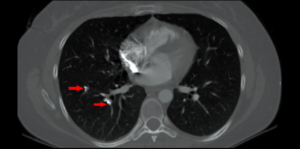

CT axial bone window